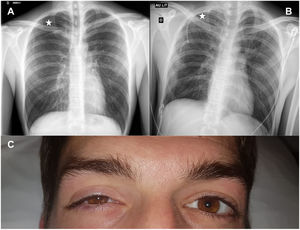

A 27-year-old man was admitted for a first episode of spontaneous apical right pneumothorax (chest X-ray, Fig. 1A). The patient reported no relevant medical history except cannabis use. We inserted an 8.5 French pigtail catheter in the pleural space (Monaldi position). No adverse events occurred during pleural drainage (local anesthesia). Chest X-ray assessed the correct chest tube position and complete lung re-expansion (Fig. 1B). 24¿;h after chest drain insertion, the patient presented ipsilateral palpebral ptosis with enophthalmos and myosis occurred (Fig. 1C): a pathognomonic triad defines Horner’s syndrome. A brain and cervical magnetic resonance angiography and a chest computed tomography did not reveal any lesion to explain Horner’s syndrome. The right pleural drain was removed as soon as pulmonary re-expansion. At hospital discharge, the patient suffered from persistent right myosis and ptosis.

Exceptional Horner’s syndrome cases could occur after a central or peripheral sympathetic pathway lesion (stellate ganglion) due to a chest tube.